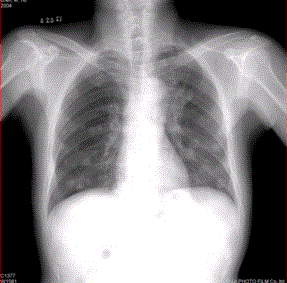

问题 患者男,45岁,因肝硬化、肝癌行肝移植术后6个月,咳嗽2周,来院复查。CR及CT影像如下图。 肺内转移结节可为

选项 A.弥漫性粟粒结节 B.单发结节 C.结节发生坏死形成空洞 D.钙化结节 E.带毛刺的结节 F.含脂肪成分的结节

答案 ABCDE

解析 ABCDE